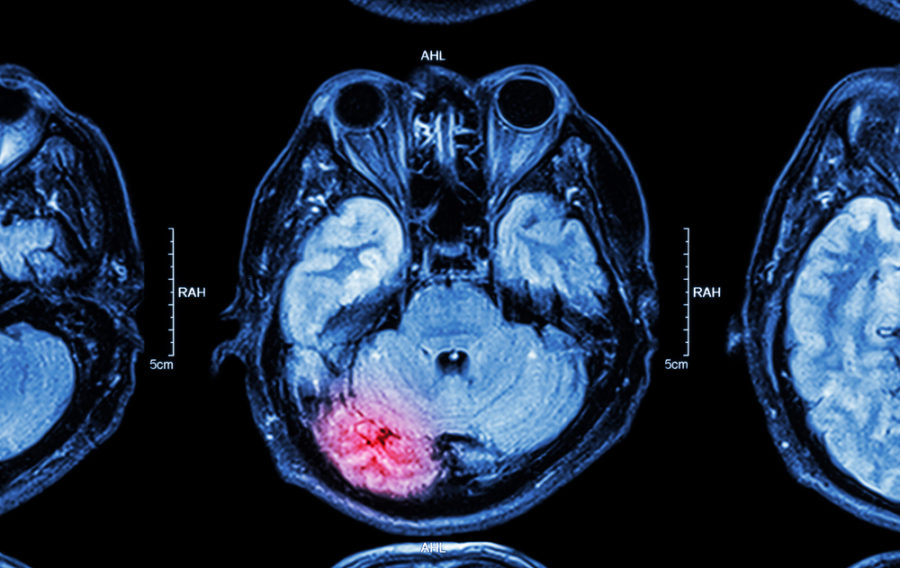

The Ministry of Defence has allocated £3.1 million for the development of the world’s first mobile magnetoencephalography (MEG) brain scanner, a project designed to provide real-time measurement of the neurological effects of blast exposure on military personnel. This investment in quantum technology aims to deliver critical insights that will inform new safety protocols and enhance the protection of service members during training and operations.

The new system will be developed by Cerca Magnetics, a spin-out company from the University of Nottingham. It will be utilised by the Defence Medical Services, part of Cyber & Specialist Operations Command, in a collaborative research programme with scientists from the Universities of Nottingham and Birmingham. A key feature of the scanner is its mobility, which allows for deployment directly to military training ranges, field hospitals, and rehabilitation centres. This capability addresses a significant challenge in military medicine: the subtle and often transient nature of brain function changes following blast exposure, which can dissipate within 24 to 48 hours and are therefore difficult to capture with conventional, static laboratory equipment.

The research programme intends to build an accurate, time-stamped understanding of the brain’s response in the minutes and hours immediately following an exposure event. By collecting this data, the Defence Medical Services expects to establish a scientific basis for creating robust policies on safe working practices. The project will investigate various weapon types and track recovery patterns to identify which personnel face the greatest risk, ultimately leading to the establishment of evidence-based exposure limits.

This initiative represents a significant step forward in applying quantum technology to a pressing defence requirement. The optically pumped magnetometer (OPM-MEG) technology at the core of the scanner has been in development for a decade, with support from the UK National Quantum Technologies Programme. The construction of the mobile system will involve UK-based technology firm Magnetic Shields Limited and US-based atomic device company QuSpin.

The project not only reinforces the UK’s position in defence science and brain imaging but also has potential applications beyond the military sector, including research into sports-related concussion, dementia, and epilepsy. The mobile MEG system is scheduled to be fully operational by 31st March 2026, marking a critical milestone for both UK defence innovation and the protection of its armed forces.